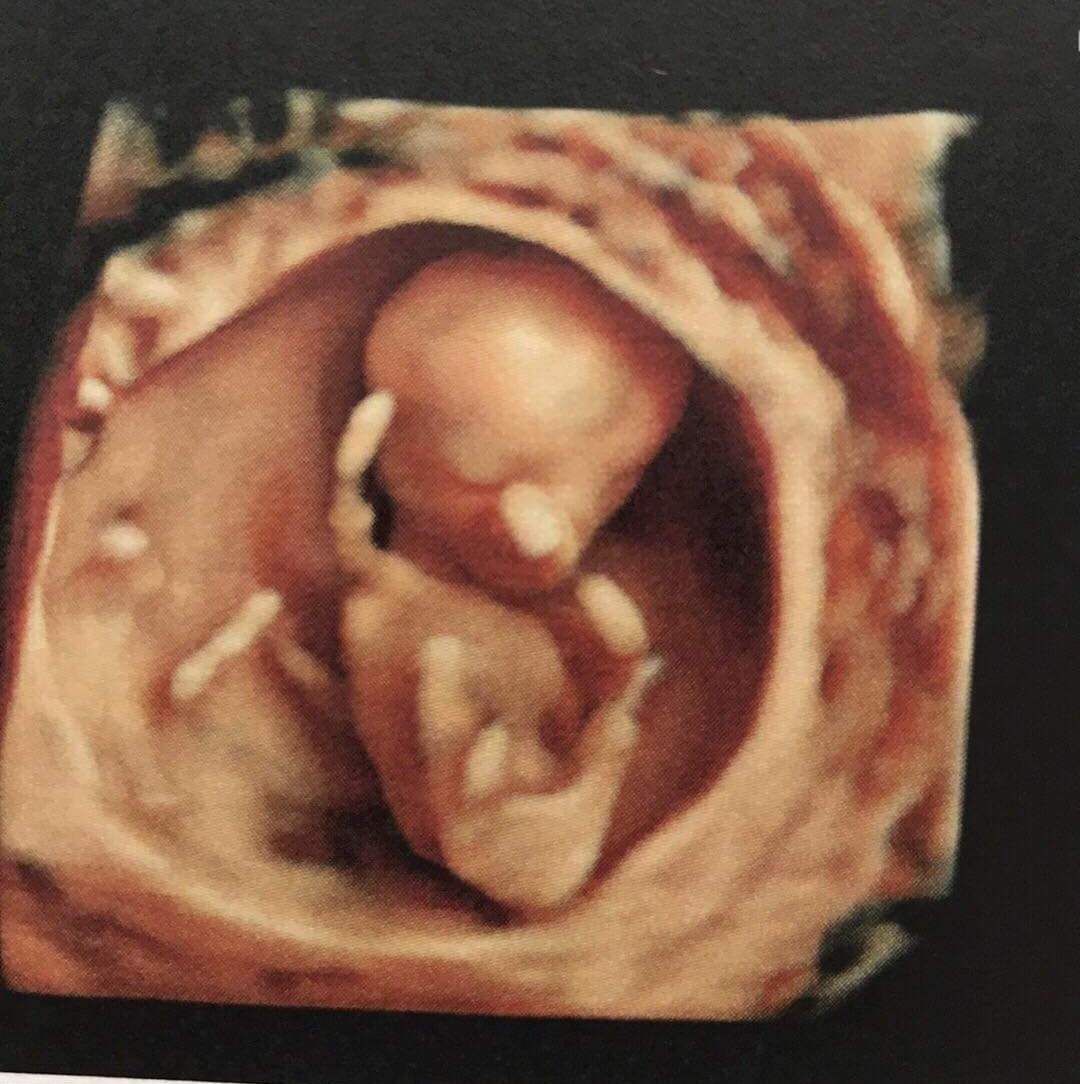

Jeeeej czyli moj bąbello wyglada tak jal twoj teraz ❤️❤️ bo taki sam termin ❤️

Bozw jakie cudowne to zdjecie z usg! ❤️ Słyszałaś serduszko?

Ja właśnie dostalam od przyjaciolki zdjęcie z prenatalnych... W 12 tyg. Boze zakochalam sie. Takie cudowne. Juz sie nie moge doczekac... Patrzcie:

Zobacz załącznik 1113401

Piękne !!! Tak słyszałam puszczał mi serduszko i w tedy oczywiście łzy mi poleciały 😭🥰 jak ten sam tydzień mamy to Twój szkrab wygląd teraz tak samo ahhh piękne zdjęcia już się nie mogę doczekać kolejne wizyty 😂 jak wcześniej się bałam tych wizyt tak teraz już się nie mogę doczekać aż znów zobaczę bobo ❤️🥰😁